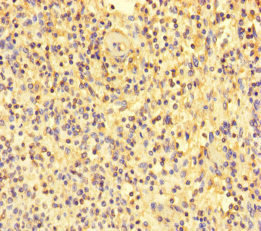

Immunohistochemistry of paraffin-embedded human tonsil tissue using CSB-PA014755LA01HU at dilution of 1:100

Immunohistochemistry of paraffin-embedded human spleen tissue using CSB-PA014755LA01HU at dilution of 1:100